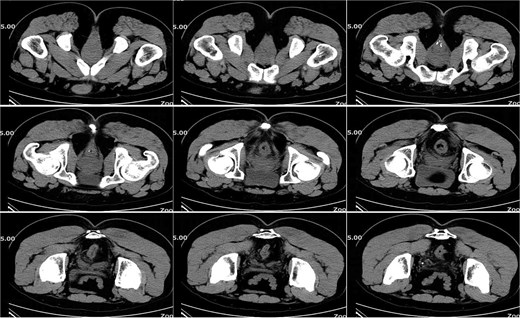

On postoperative Day 21, a follow-up pelvic CT scan indicated local gas accumulation around the rectum, suggesting an absorption phase of the infection (Fig. 4). By postoperative Day 28, a pelvic CT scan demonstrated minor gas accumulation at the anterior edge of the rectosigmoid junction, consistent with infection resolution and gas absorption in the surrounding area (Fig. 5). By postoperative Day 49, a pelvic CT scan revealed no abnormal density shadows in the perianal skin and soft tissues, with preserved fat planes (Fig. 6), indicating complete resolution of the perirectal infection and restoration of normal clinical status.